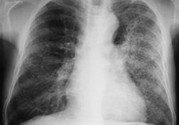

小兒肺炎的癥狀表現(xiàn)有哪些?小兒肺炎應該怎么治療?

小兒肺炎在孩子中是很容易發(fā)生的,孩子身體免疫力比較低,容易受到傳染。那么,小兒肺炎的癥狀表現(xiàn)有哪些呢?

小兒肺炎癥狀

早期癥狀: 流清鼻涕、鼻塞、噴嚏等,也可用流淚、微咳或咽部不適,可在3~4天內(nèi)自然痊愈。開始為頻繁的剌激性干咳,隨之咽喉部出現(xiàn)痰鳴音,咳嗽時可伴有嘔吐、嗆奶。有時淋巴結可稍腫大。呼吸表淺增快,鼻扇,部份患兒口周、指甲輕度發(fā)紺。除呼吸道癥狀外伴有精神萎靡、煩躁不安、食欲不振、哆嗦、腹瀉等全身癥狀。在嬰幼兒容易引起嘔吐及腹瀉。

晚期癥狀: 持續(xù)高熱、全身中毒等癥狀嚴重,且伴有其它臟器功能損害。伴有冷感,頭痛、全身無力、食欲銳減、睡眠不安等,不久即可因部微紅,發(fā)生皰疹和潰瘍,有時紅腫明顯,波及扁桃體,出現(xiàn)濾泡性膿性滲出物,咽痛和全身癥狀均加征,鼻咽分泌物從稀薄變成粘稠。